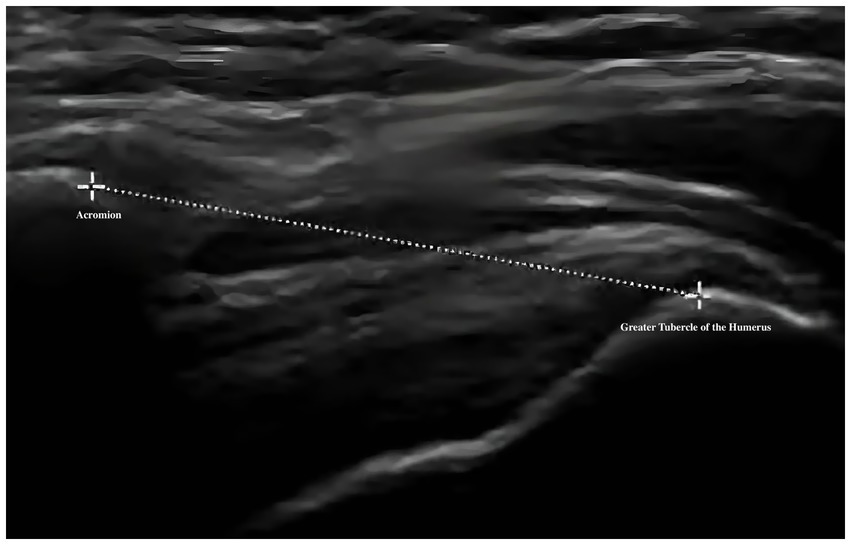

The primary outcome is pain intensity, assessed using the VAS, a widely recognized and validated tool. VAS scores will be recorded at baseline, at 2 and 4 weeks during treatment, and again at a 1-month follow-up after completion of the intervention. Secondary outcomes assess shoulder joint function across four domains. First, ROM will be measured to evaluate mobility of the affected shoulder. Second, the absolute vertical distance difference between the medial superior angle of the scapula on the affected side and the second thoracic spinous process will be recorded. Third, musculoskeletal ultrasound will be used to assess five key indicators: presence of effusion around the long head of the biceps tendon sheath, calcification in the supraspinatus muscle, calcification at the insertion of the subscapularis tendon, subdeltoid bursa thickness (in millimeters), and the distance from the acromion to the greater tuberosity of the humerus. Lastly, the MBI will be used to evaluate overall independence in daily living activities. Covariates include age, sex, body mass index (BMI), stroke type (hemorrhagic or ischemic), and time since stroke onset. All outcome measures will be collected at baseline, 2 weeks, and 4 weeks after treatment begins. A follow-up VAS will be conducted 1 month post-intervention to assess the sustained effects of DPS in relieving post-stroke shoulder pain. The physical function assessments will be performed by trained evaluators blinded to treatment allocation, and data analysis will be conducted by statisticians also blinded to group assignments.

For musculoskeletal ultrasound outcomes, four key indicators will be analyzed: (1) distance from the acromion to the greater tuberosity of the humerus and (2) thickness of the subdeltoid bursa will be treated as continuous variables and analyzed using the same approach as other quantitative measures—independent t-tests or Mann–Whitney U tests for between-group comparisons, and repeated measures ANOVA or Friedman tests for within-group changes. (3) Calcifications in the supraspinatus tendon and (4) effusion around the long head of the biceps tendon sheath will be treated as binary variables (presence/absence) and compared between groups using chi-square tests. All ultrasound images will be independently reviewed by two experienced sonographers blinded to group allocation. Inter-rater reliability will be evaluated using Cohen’s kappa for categorical variables and intraclass correlation coefficients (ICC) for continuous variables. Any discrepancies will be resolved by consensus discussion.

Musculoskeletal ultrasound is a practical and noninvasive method for detecting structural abnormalities commonly associated with PSSP. Key indicators include the distance from the acromion to the greater tuberosity of the humerus (Figure 9), effusion around the long head of the biceps tendon sheath (Figure 10), calcification in the supraspinatus (Figure 11) and subscapularis tendons, and increased thickness of the subdeltoid bursa (Figure 12). Effusion around the biceps tendon sheath often reflects inflammation or tendinopathy, which can contribute to pain and limited mobility. Calcifications in the supraspinatus and subscapularis tendons are typically associated with chronic rotator cuff conditions that result in impingement and reduced range of motion. Thickening of the subdeltoid bursa is suggestive of bursitis, a frequent source of discomfort in PSSP patients (21).

Figure 9

Ultrasound image showing a cross-sectional view of the shoulder. A dotted line indicates the distance from the acromion to the greater tubercle of the humerus.

Figure 9. Distance from the acromion to the greater tuberosity of the humerus.